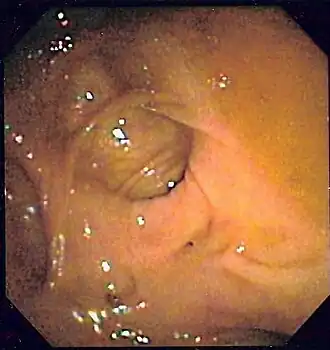

Tabla 4. Criterios diagnósticos endoscópicos de localización de la hemorragia en el colon (Zuckerman y Prakash 1998,[6]​ Green et al. 2005[113])

Grado de probabilidad Tipo Criterio

Definitivo 1 Lesión con hemorragia activa: visualización de emanación activa de sangre de un lugar específico o de una lesión fácilmente identificable, hemorragia que persiste a pesar de haber irrigado profusamente la zona.

Definitivo 2 Lesión no hemorrágica con vaso expuesto visible: lesión muy localizada protuberante de coloración púrpura o roja.

Definitivo 3 Lesión con coágulo adherido: coágulo denso y adherido que persiste a pesar de lavado profuso del mismo.

Presuntivo 4 Sangre reciente localizada en un segmento determinado del colon situado en la misma localización que una lesión potencialmente sangrante o distal a dicha lesión.

Presuntivo 5 Divertículo ulcerado con sangre reciente en una zona próxima.

Probable 6 Ausencia de sangre reciente en íleon terminal con sangre presente en el colon.

Como un alto porcentaje de hemorragias bajas ceden espontáneamente, hay muchos diagnósticos endoscópicos dudosos cuando no se identifica una lesión hemorrágica activa o un coágulo adherido evidentes. Es frecuente, por ejemplo, que se vean varios divérticulos y además una angiodisplasia, o unas hemorroides internas congestivas, sin signos de sangrado ni coágulo adherido en ninguna de estas lesiones. En ocasiones, será la presencia de sangre en un nivel u otro del colon junto con las lesiones potencialmente sangrantes lo que nos determine la impresión diagnóstica.[7]